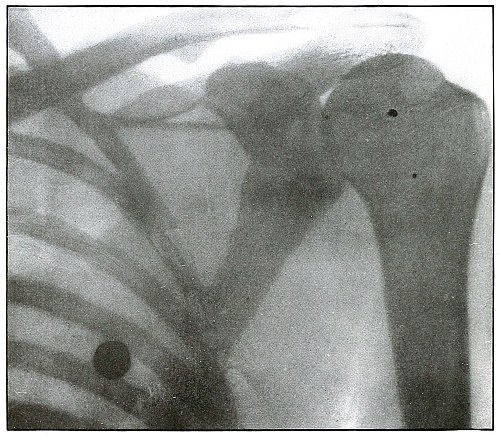

82.[Pg 5] Gunshot wound, shoulder 174

83. Gunshot wound, shoulder 176

84. Gunshot wound, shoulder 178

85. Gunshot wound, shoulder 180